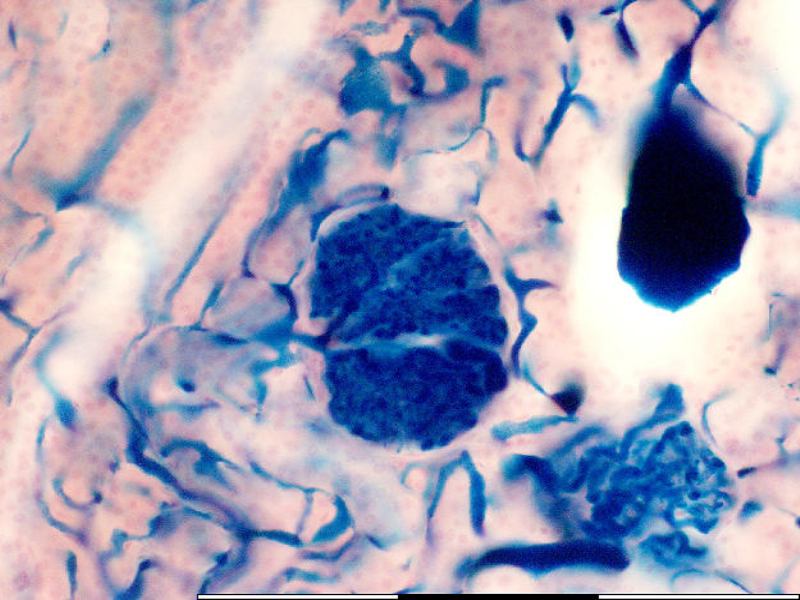

Portal vein vs Central vein

The portal vein is part of the portal triad. It has an associated artery and bile duct. The central vein has no other structures around it, and the endothelium is indistinct. You can most the times also see the sinusoids opening up into the central vein.

Compare the central vein and portal triad...

Blood flow

What happens

to blood

going

into the liver?

From hepatic artery and vein

Mix

Flow towards the central vein